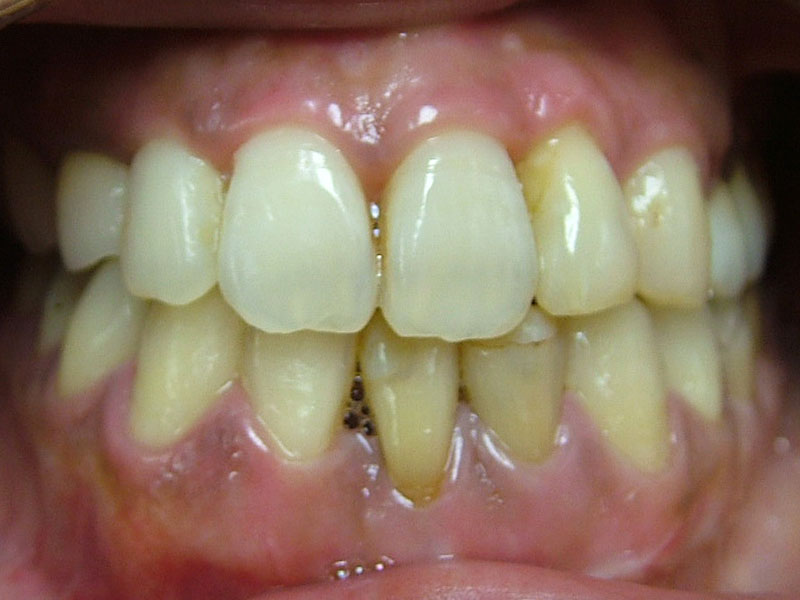

術後

トータルの治療期間は3年くらいでしたが、包括歯科治療(虫歯治療、歯周病治療、抜歯、矯正治療、歯内治療、修復治療、メンテナンス)を1人の歯科医が行い、まずまずの治療を行うことができたのではないかと思います。患者さんも十分に満足されました。

ただ、後年(2年後)、下前歯はブラックトライアングルの改善ならびに保定も兼ねて、3本前歯は連結修復を行いました。4か月メンテナンスに移行です。

術後10年後

メンテナンスのみで、今のところ再治療を行った歯はありません。うまくコントロールされていると思います。ただ、鼻性由来の両側副鼻腔炎を患ってたので、耳鼻科への来院を促しました。